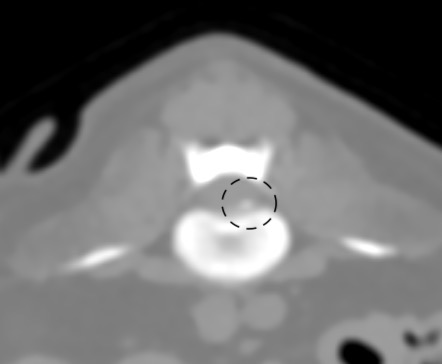

第5-6腰椎間椎間板の脊柱管への突出・石灰化が認められ、左側での脊髄の圧迫所見が認められました。*黒線で囲った部位

責任病変が第5-6腰椎間・第3-4腰椎間の二か所である椎間板ヘルニアと診断しました。